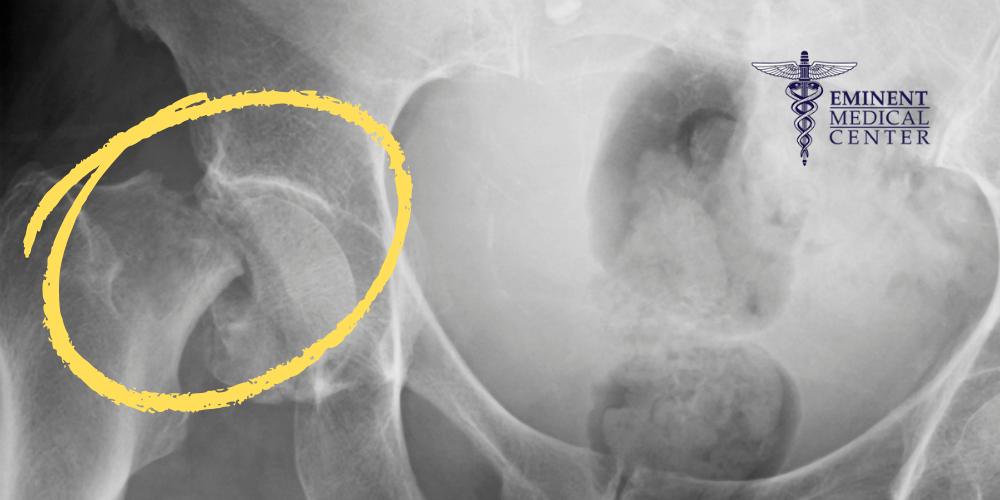

A hip fracture is a serious injury involving a break in the upper part of the femur, or thigh bone, near the hip joint. Most hip fractures occur in the femoral neck or head, critical areas within the ball-and-socket joint that support the body’s weight and mobility. These fractures can also happen in the intertrochanteric or subtrochanteric regions, which involve the greater and lesser trochanters of the hip bone.

Femoral Neck Fracture Surgery

Femoral neck fractures occur just below the femoral head in the narrow region connecting the head of the femur to the rest of the thigh bone. This area is especially vulnerable to disrupted blood flow, increasing the risk of avascular necrosis if not treated quickly. These fractures are common in older patients with osteoporotic bone and can be displaced or nondisplaced.

Surgical treatment for femoral neck fractures may involve internal fixation using metal screws or a partial hip replacement, depending on the patient’s age, activity level, and overall health. If the patient has more severe or displaced fractures, their surgeon may recommend a total hip replacement to reduce pain and restore function.